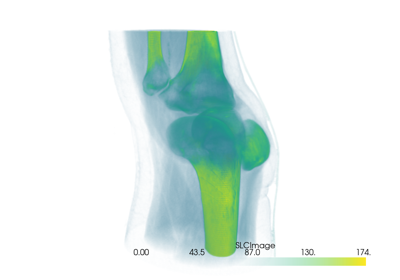

Filtering#

These examples show case various mesh analysis and filtering routines present in the Filters module. Explore these demos to perform tasks such as:

Slicing and cutting meshes

Computing mesh properties like volume, area, and surface normals

Mesh decimation

Extract regions of one mesh using another mesh’s surface

Ray tracing through surface meshes

Resampling and interpolating scalar/vector values across meshes

Integrating a vector field to generate streamlines

Smoothing surfaces